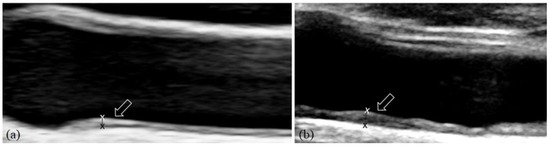

The head and neck and oral maxillofacial regions are composed of complex anatomical structures and contain various types of tissues. Radiological examination is one of the most important and widely used clinical approaches for understanding these regions. Advances in medical imaging acquisition and imaging analysis, including artificial intelligence, allow researchers and clinicians to understand the underlying physiology and pathology of these regions. These advances also offer the potential to integrate research findings to clinical practice.